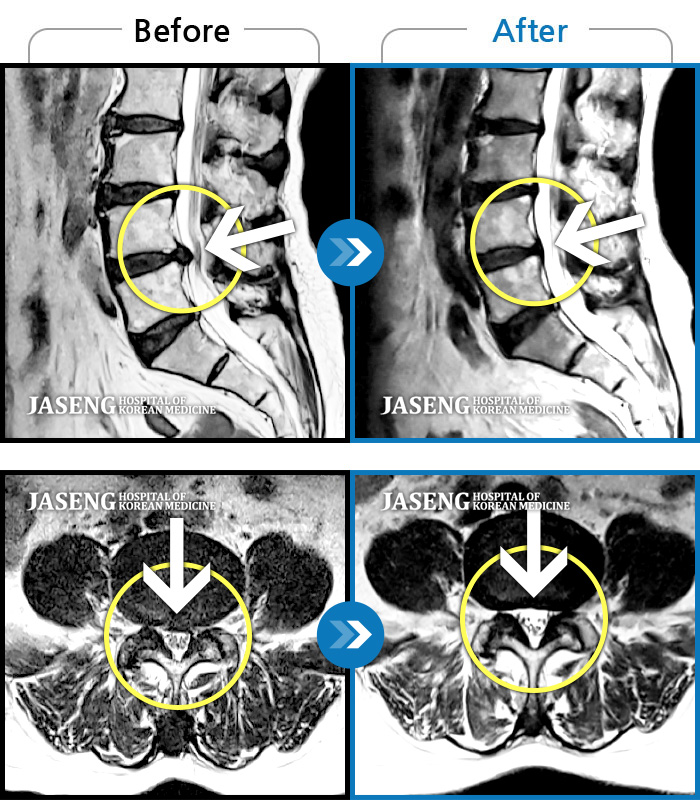

MRI 치료사례

허리통증으로 일상이 멈췄다.